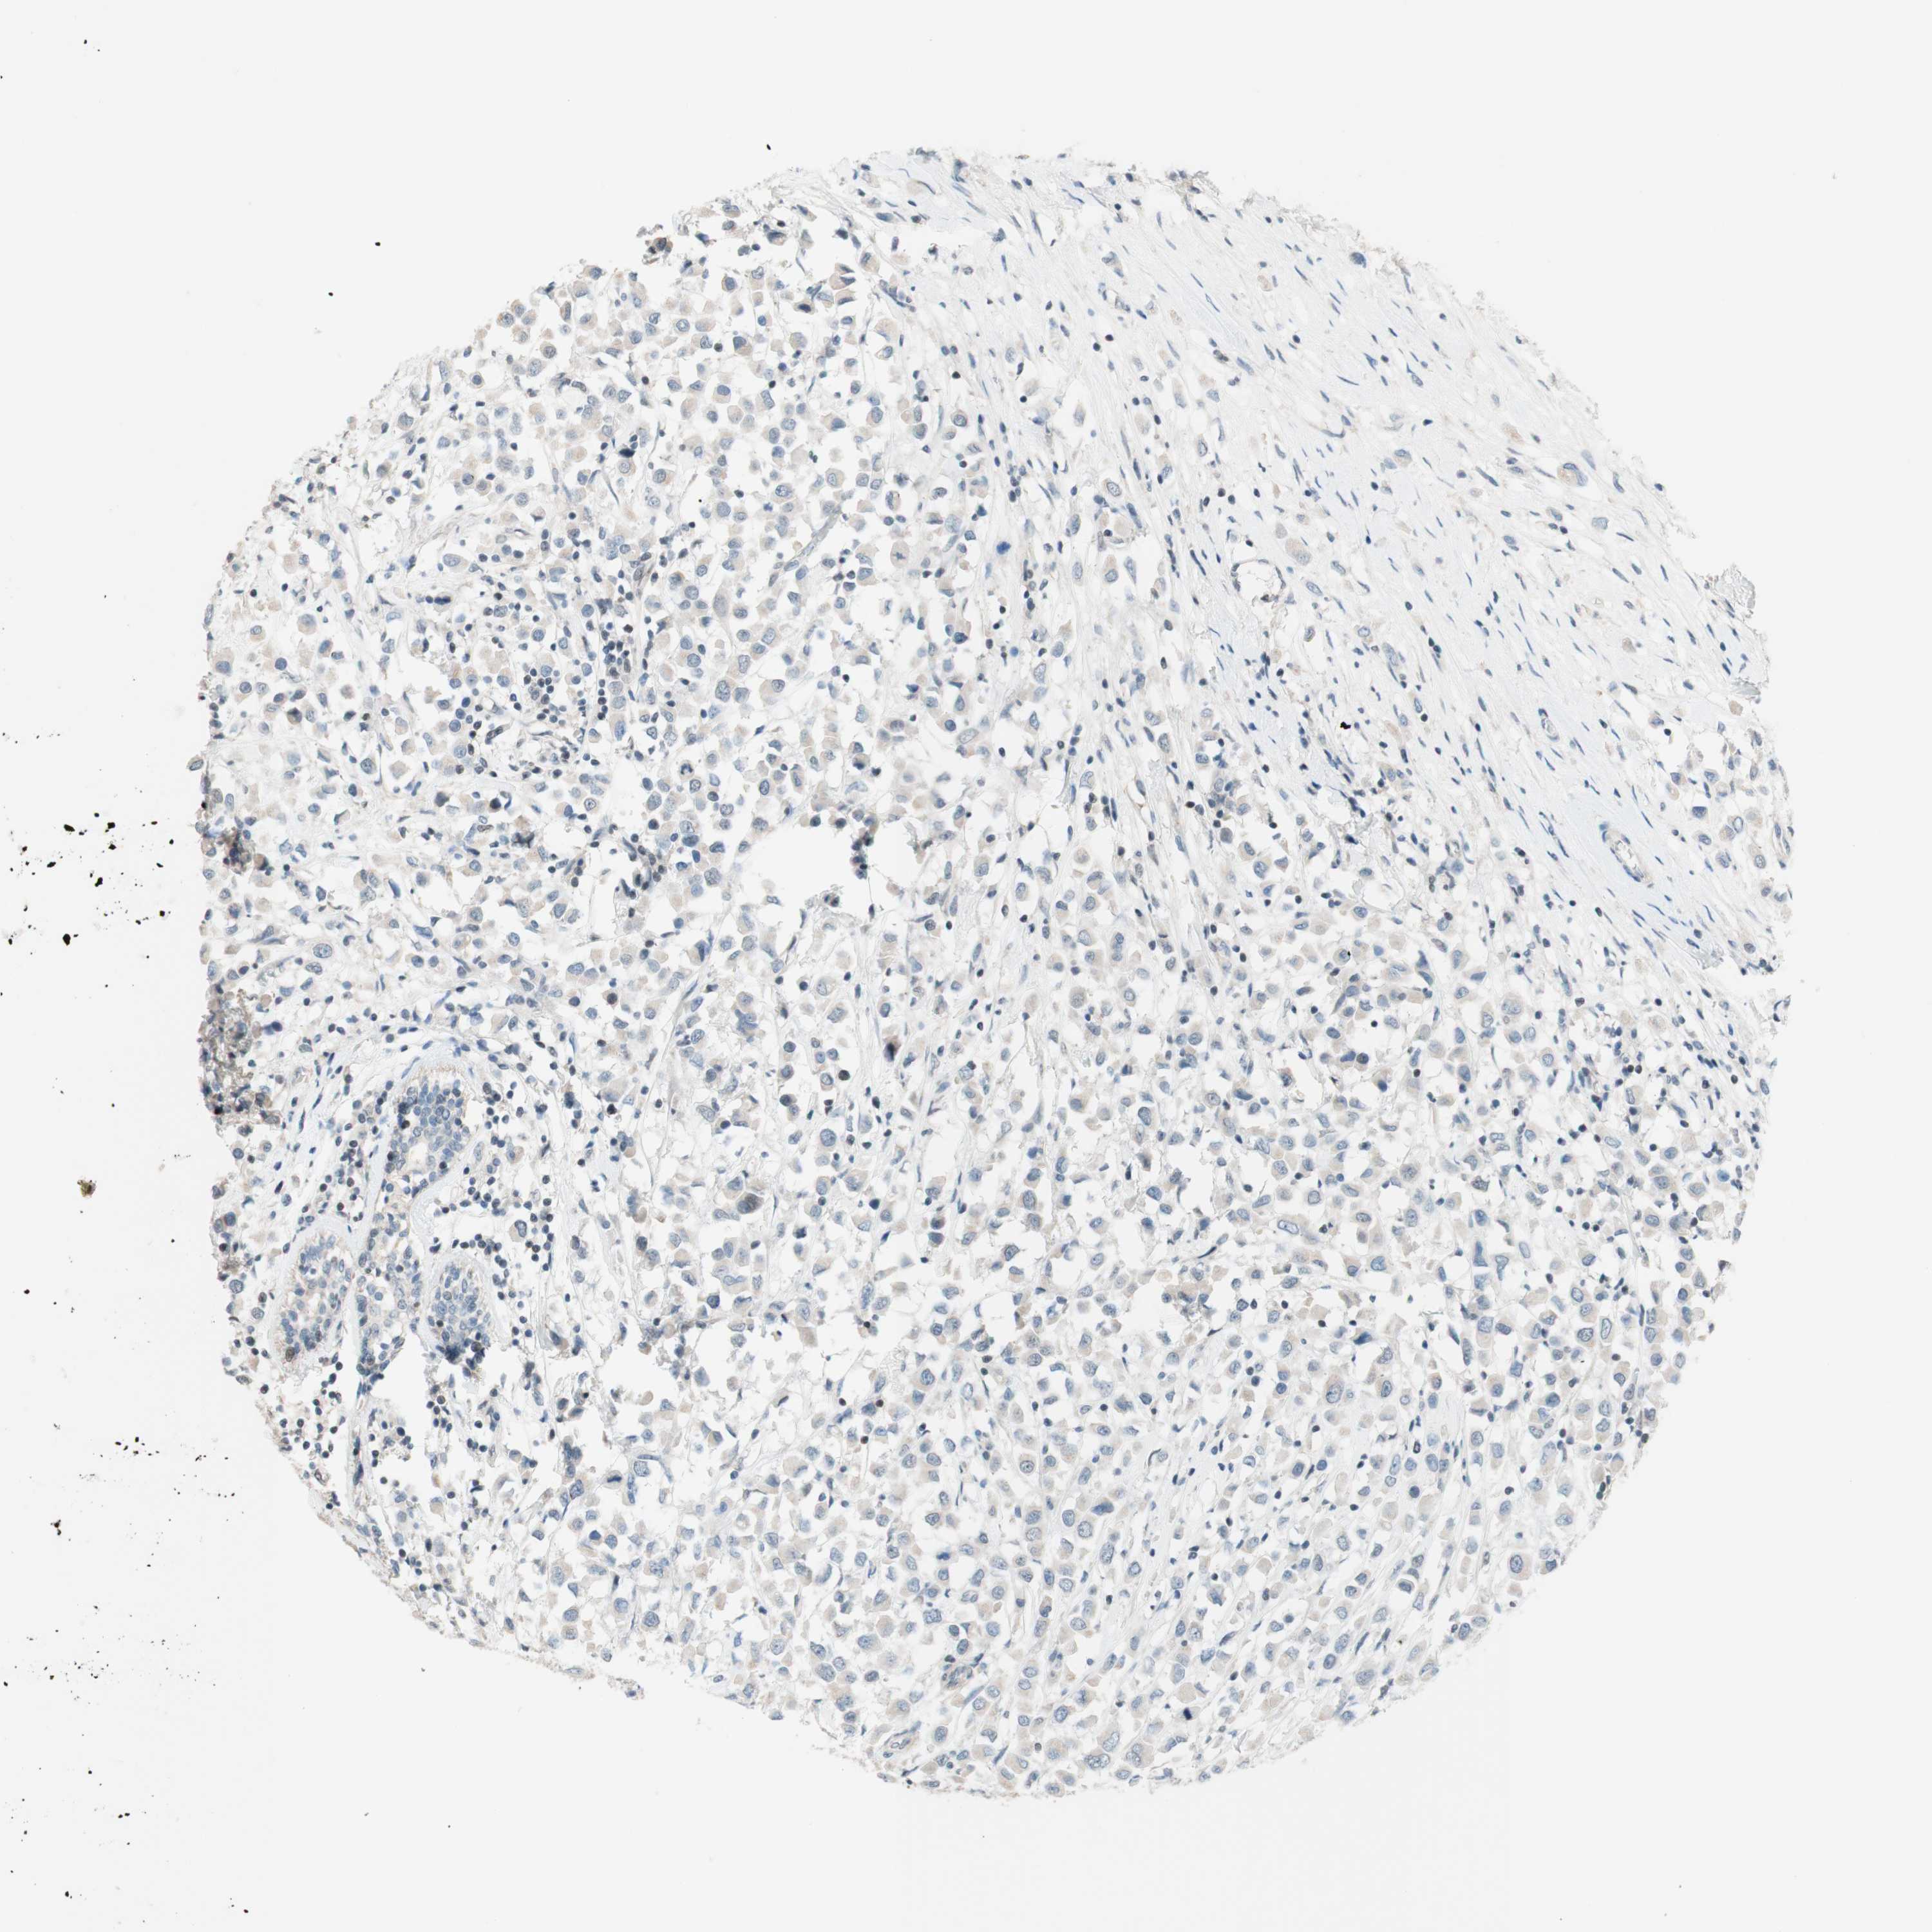

JPH1

CANCER BREAST CANCER Show tissue menu

BRCA TCGA BRCA VALIDATION PROTEIN EXPRESSION

Breast cancer

Human cancer

JPH1 is not prognostic in Breast Invasive Carcinoma (TCGA)